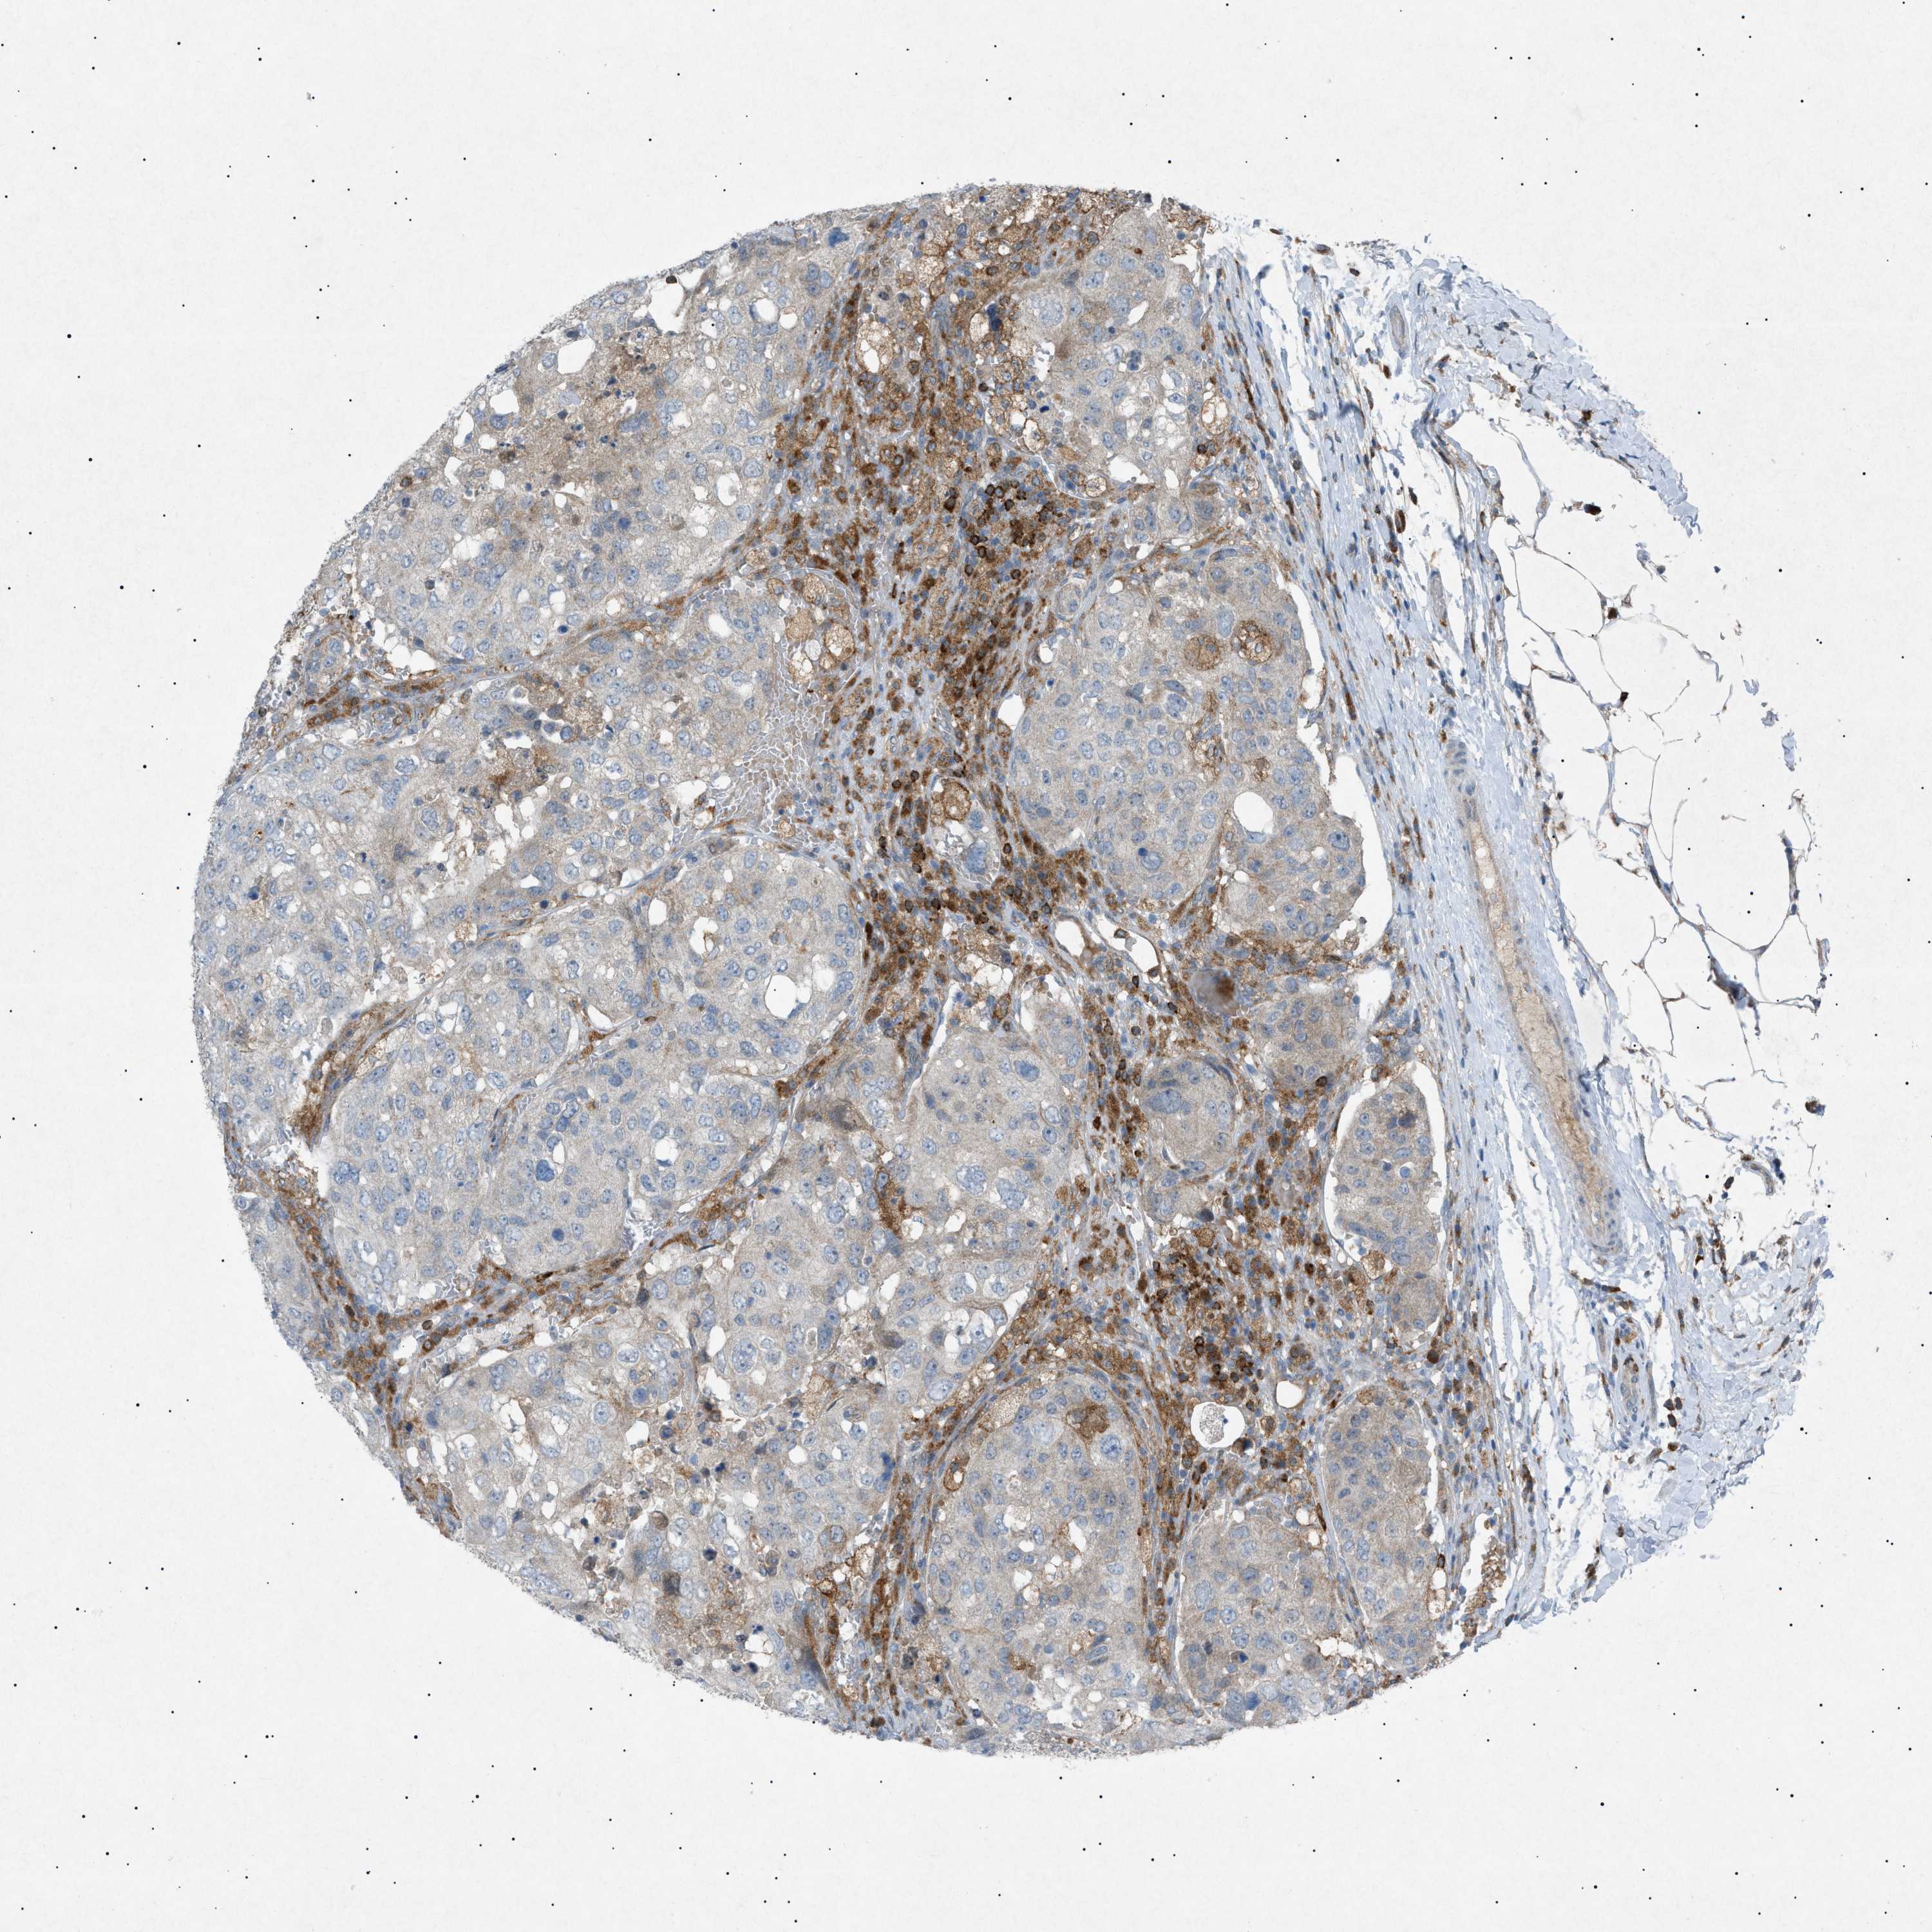

UROTHELIAL CANCER - Protein expressioni

A mouse-over function shows sample information and annotation data. Click on an image to view it in a full screen mode. Samples can be filtered based on level of antibody staining by selecting one or several of the following categories: high, medium, low and not detected. The assay and annotation is described here.

Note that samples used for immunohistochemistry by the Human Protein Atlas do not correspond to samples in the TCGA dataset.

Antibody stainingi

Antibody staining in the annotated cell types in the current human tissue is reported as not detected, low, medium, or high, based on conventional immunohistochemistry profiling in selected tissues. This score is based on the combination of the staining intensity and fraction of stained cells.

Each image is clickable and will lead to virtual microscopy that enables deeper exploration of all samples and also displays staining intensity scores, fraction scores and subcellular localization as well as patient and tissue information for each sample.

Antibody HPA001198

Antibody HPA002028

Antibody CAB016689

Antibody CAB080300

Staining

High

Medium

Low

Not detected

Intensity

Strong

Moderate

Weak

Negative

Quantity

>75%

75%-25%

<25%

None

Location

Nuclear

Cytoplasmic/membranous

Cytoplasmic/membranous,nuclear

Urothelial carcinoma, High grade

Urothelial carcinoma, Low grade

Adenocarcinoma, NOS